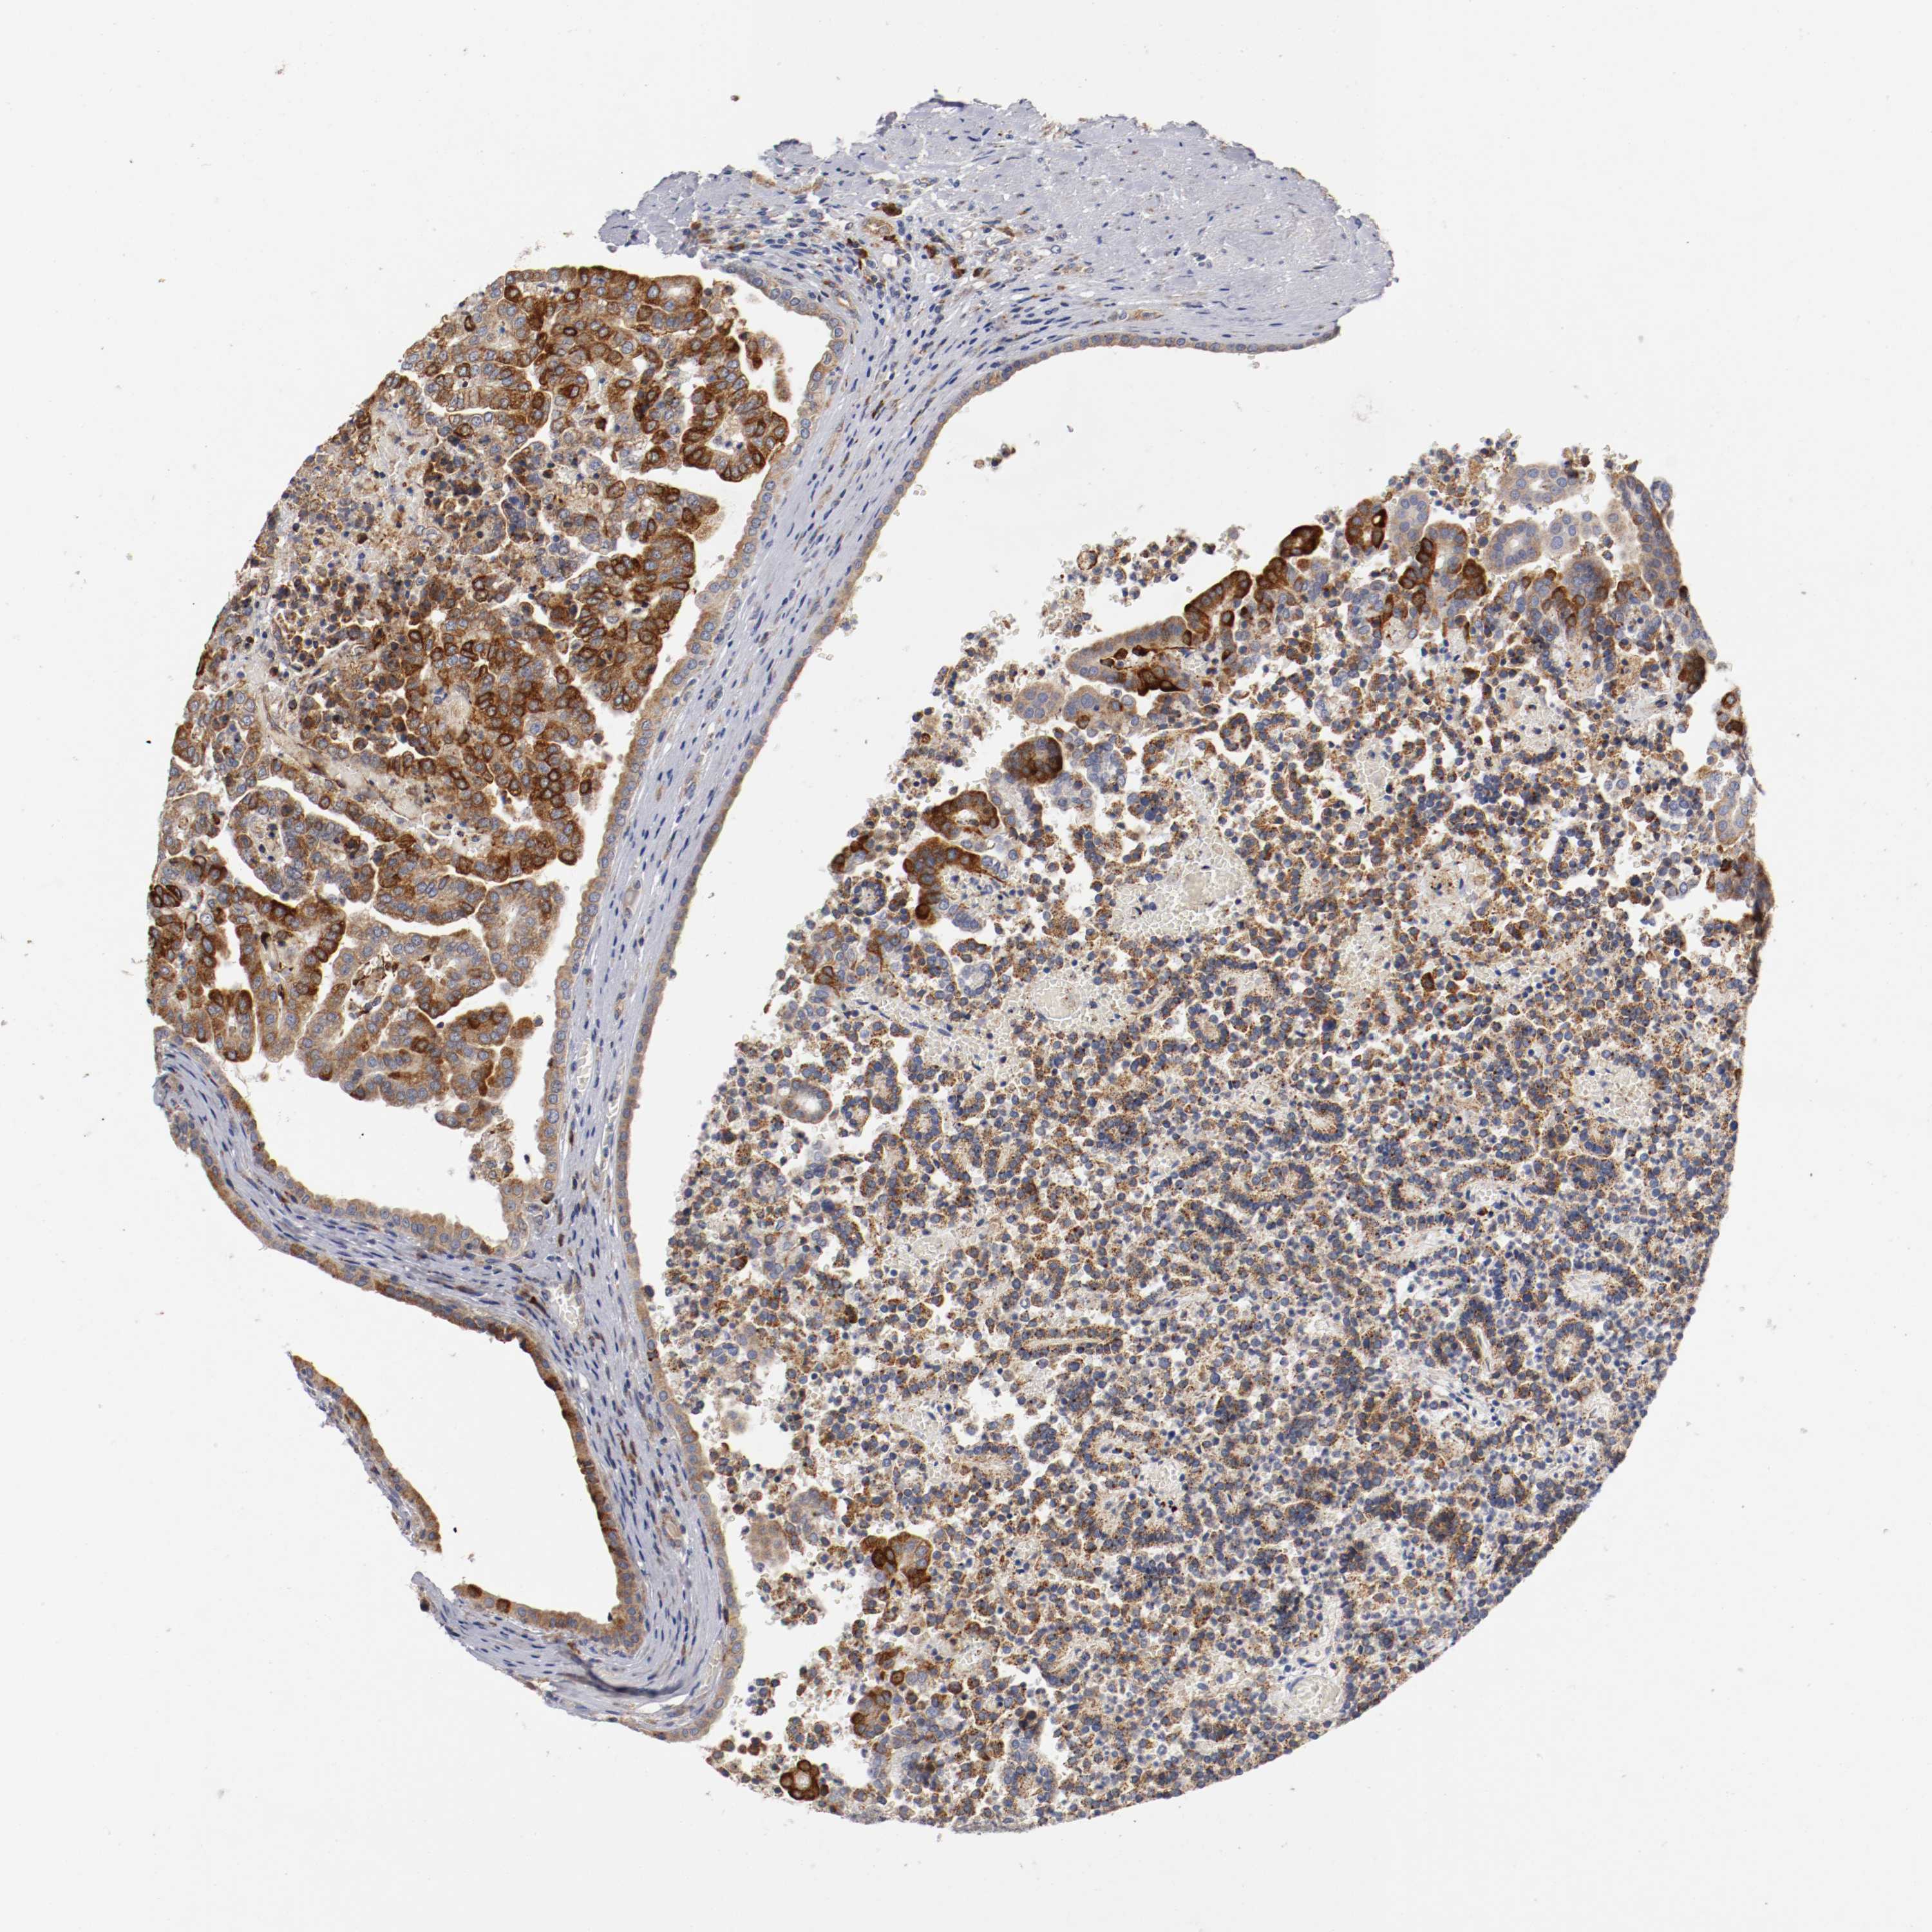

KIDNEY RENAL CLEAR CELL CARCINOMA (TCGA) - Interactive survival scatter ploti

The Survival Scatter plot shows the clinical status (i.e. dead or alive) for all individuals in the patient cohort, based on the same data that underlies the corresponding Kaplan-Meier plots. Patients that are alive at last time for follow-up are shown in blue and patients who have died during the study are shown in red.

The x-axis shows the expression levels (FPKM) of the investigated gene in the tumor tissue at the time of diagnosis. The y-axis shows the follow-up time after diagnosis (years). Both axes are complimented with kernel density curves demonstrating the data density over the axes. The top density plot shows the expression levels (FPKM) distribution among dead (red) and alive patients (blue). The right density plot shows the data density of the survived years of dead patients with high and low expression levels respectively, stratified using the cutoff indicated by the vertical dashed line through the Survival Scatter plot. This cutoff is automatically defined based on the FPKM cutoff that minimizes the p-score. The cutoff can be changed by dragging the vertical line or by entering a cutoff value in the square labeled "Current cut-off".

Under the Survival Scatter plot the p-score landscape (black curve; left axis) is shown together with dead median separation (red curve; right axis). Dead median separation is the difference in median mRNA expression between patients who have died with high and low expression, respectively. It is calculated as follows: median FPKM expression of dead patients with high expression - median FPKM expression of dead patients with low expression. This is intended to aid the user in visually exploring custom cutoffs and the associated p-scores and dead median separation.

Individual patient data is displayed and can be filtered by clicking on one or more of the category buttons on the top of the page. Categories describing expression level and patient information include: high, low, alive, dead, female, male and tumor stages. The scale of the x-axis can be toggled between linear and log-scale by clicking on the "x log" button. Mouse-over function shows TCGA ID, patient information and mRNA expression (FPKM) for each patient.

& Survival analysisi

Kaplan-Meier plots summarize results from analysis of correlation between mRNA expression level and patient survival. Patients were divided based on level of expression into one of the two groups "low" (under cut off) or "high" (over cut off). X-axis shows time for survival (years) and y-axis shows the probability of survival, where 1.0 corresponds to 100 percent.

TRAF2 is not prognostic in Kidney Renal Clear Cell Carcinoma (TCGA)

Best expression cut offi

Based on the FPKM value of each gene, patients were classified into two groups and association between prognosis (survival) and gene expression (FPKM) was examined. The best expression cut-off refers the FPKM value that yields maximal difference with regard to survival between the two groups at the lowest log-rank P-value. Best expression cut-off was selected based on survival analysis .

When clicking on this number, the vertical dashed line indicating cut-off, the interactive survival plot, and the Kaplan-Meier curve will be adjusted to show results based on the best expression cut-off.

: 18

Median expressioni

Median expression refers to the median FPKM value calculated based on the gene expression (FPKM) data from all patients in this dataset. When clicking on this number, the vertical dashed line indicating cut-off, the interactive survival plot, and the Kaplan-Meier curve will be adjusted to show results based on the median expression.

: N/A

Median follow up timei

Median follow up time refers to the median time (years) after diagnosis with this type of cancer, based on clinical data from all patients in this dataset.

P scorei

Log-rank P value for Kaplan-Meier plot showing results from analysis of correlation between mRNA expression level and patient survival.

N/A

5-year survival highi

5-year survival for patients with higher expression than the expression cutoff.

For melanoma and glioma, 3-year survival is shown.

5-year survival lowi

5-year survival for patients with lower expression than the expression cutoff.

TCGA RNA samplesi

RNA-seq data is reported as average FPKM (number Fragments Per Kilobase of exon per Million reads), generated by the The Cancer Genome Atlas (TCGA) .

Normal distribution across the dataset is visualized with box plots, shown as median and 25th and 75th percentiles. Points are displayed as outliers if they are above or below 1.5 times the interquartile range. FPKM values of the individual samples are presented next to the box plot.

Average pTPM 15.3

Number of samples 521